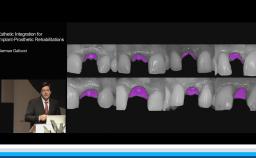

German Gallucci